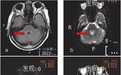

MRI 如图(图 a:T2 FLAIR 序列;图 b:T2 加权成像;图 c:DWI;图 d:ADC)

临床感染症状,mri T2像四脑室壁信号增高,弥散受限,提示室管膜炎,支持病毒感染,巨细胞病毒或流感病毒感染可能,其次链球菌感染不除外

复习病史,考虑中枢神经系统感染性疾病、脑疝;复习影像学检查,第四脑室周围信号异常,考虑炎症性病变,更重要的是第四脑室扩张(脑积水)。综上,考虑感染性孤立性第四脑室。治疗:控制颅内感染;择期行脑室腹腔分流术

头颅 MRI 提示软脑膜、室管膜区和脑实质多个区域信号异常,可能是多发性增强的颅内占位性病变。结合 CSF 检查结果:单核细胞增多,蛋白增多,说明可能是病毒性脑炎、自身免疫性疾病或慢性感染(如结核或真菌感染)等导致脑炎。